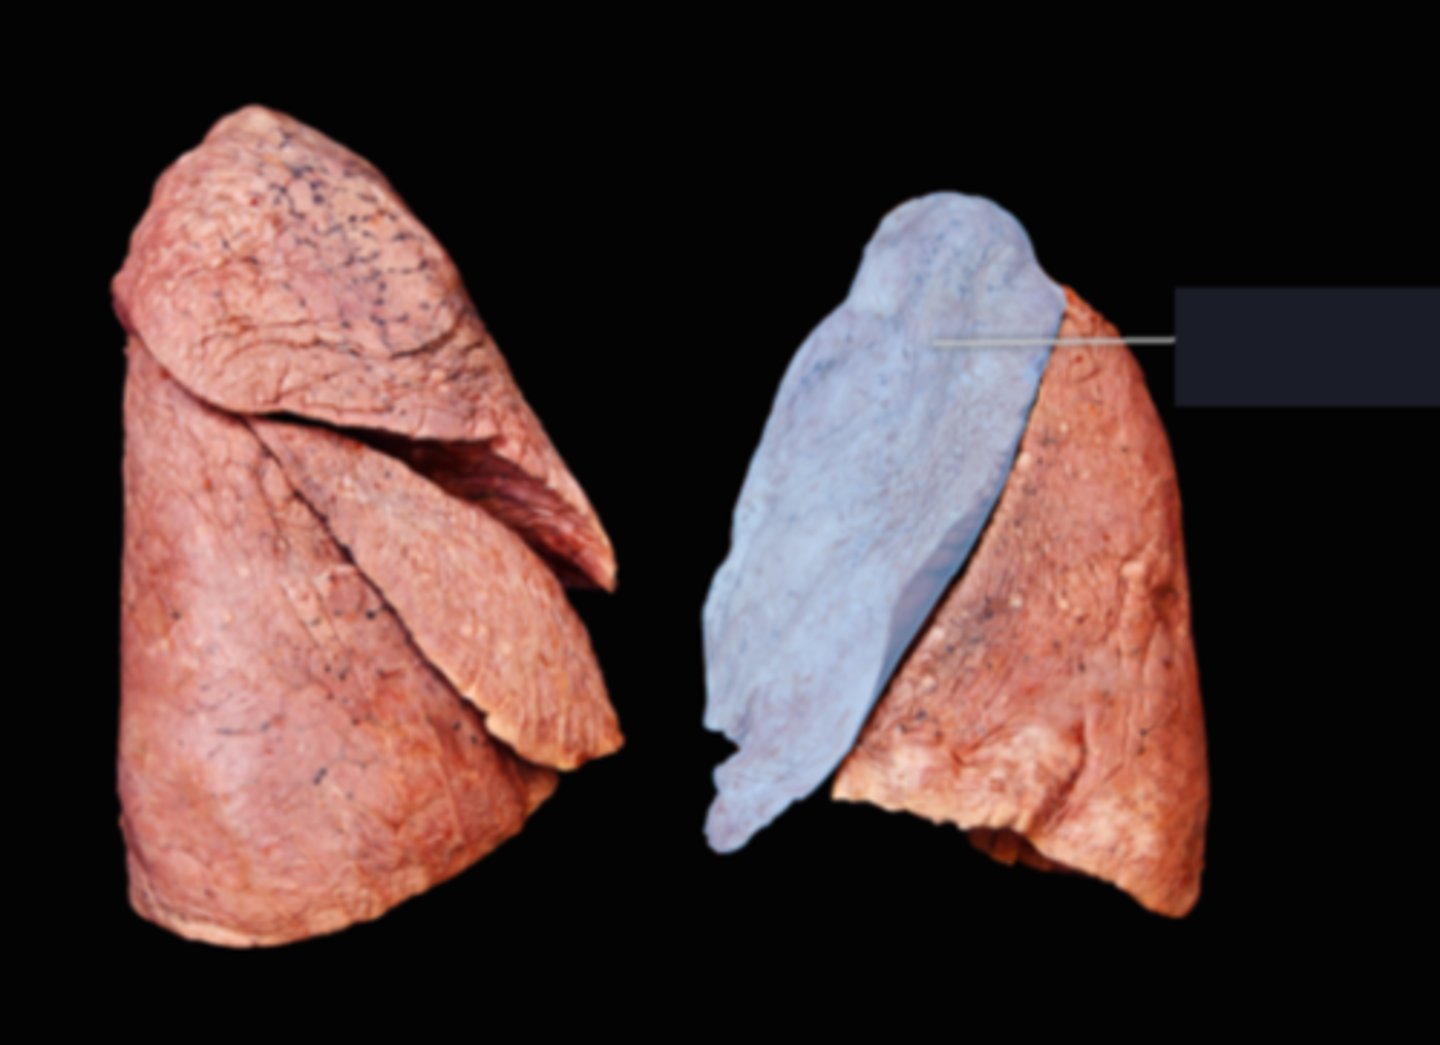

Lingula

Apex

Base/Diaphragmatic Surface

Costal Surface

Mediastinal Surface

Anterior Margin

Posterior Margin

Visceral Plurae